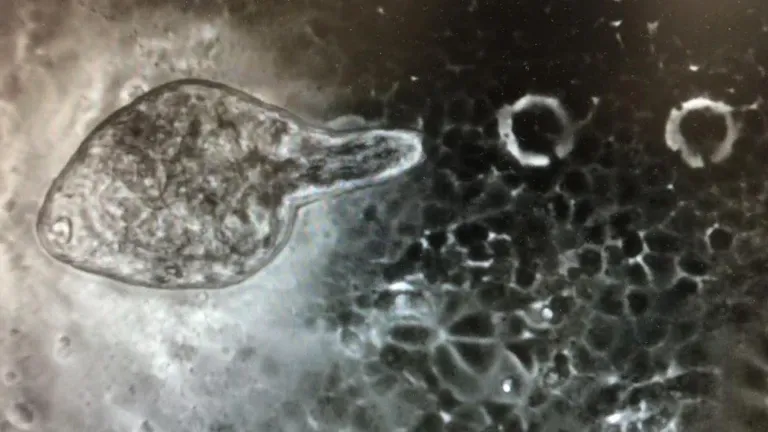

Nos ha sorprendido la investigación en la que se encuentra ahora mismo inmersa una parte del Instituto de Recursos Naturales y Agrobiología de Salamanca, el IRNASA CSIC. Casi sin querer, nos ha contado en HERRERA EN COPE SALAMANCA, su directora Mar Siles han descubierto que algunas moléculas del gusano Fasciola hepática actúan como antivirales frente al Covid y otros virus respiratorios emergentes. Han dado con ello buscando una vacuna contra este parásito que en países subdesarrollados afecta a animales y humanos. Han descubierto que en los pacientes de esos países con Covid y con el parásito en el cuerpo, la tasa de morbimortalidad era menor. El parásito por tanto ayuda a generar respuestas inmunes frente al Covid y otros virus.

Son varios caminos los que se plantean. Primero ver cuáles son las moléculas de este parásito que poseen el efecto antiviral y producirlas sistémicamente y después, aunque el Irnasa ya esta trabajando, crear una Plataforma de Cribado de Antivirales para testar antivirales que sirvan para reponer fármacos que, tanto en animales como humanos, luchen contra los virus respiratorios emergentes.